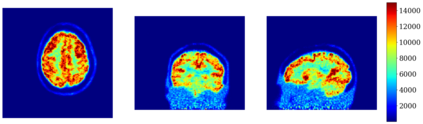

In this work, we investigate hybrid PET reconstruction algorithms based on coupling a model-based variational reconstruction and the application of a separately learnt Deep Neural Network operator (DNN) in an ADMM Plug and Play framework. Following recent results in optimization, fixed point convergence of the scheme can be achieved by enforcing an additional constraint on network parameters during learning. We propose such an ADMM algorithm and show in a realistic [18F]-FDG synthetic brain exam that the proposed scheme indeed lead experimentally to convergence to a meaningful fixed point. When the proposed constraint is not enforced during learning of the DNN, the proposed ADMM algorithm was observed experimentally not to converge.